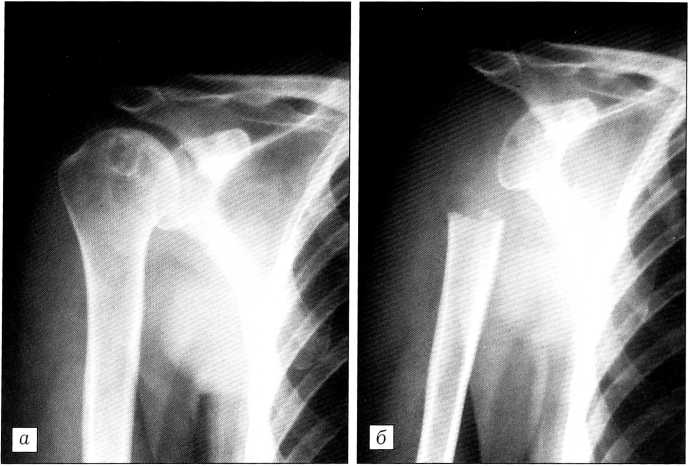

На рентгенограммах правого плечевого сустава (рис. 2) в эпифизарном отделе плечевой кости выявляется очаг деструкции ячеистого характера с единичными включениями кальция. Заключение: хондробластома. Для такого заключения были основания, так как очаг деструкции локализовался в эпифизе, что является характерным для хондробластомы и отличает ее от других опухолей. Сомнения в диагнозе могли быть вызваны возрастом больной: хотя хондробластома не исключена у людей среднего возраста, все же она более характерна и чаще всего встречается в молодом или даже подростковом возрасте. Кроме того, в анамнезе у больной — рак молочной железы, что настораживало в отношении возможного метастазирования в кость. Других патологических очагов в костях не выявлено. Трепанобиопсия больной не проводилась: надеяться на ее положительный ответ было трудно (очаг поражения мал для того, чтобы получить точно из него достаточное количество материала для исследования), а отрицательный результат не был бы доказательным.

Рис. 2. Рентгенограммы больной П. до (а) и после (б) операции.

Решено, исходя из клинической картины и рентгенологических данных, произвести больной лечебно-диагностическое вмешательство — резекцию только головки плечевой кости. Операция выполнена 9.10.91. Дефект не замещался. Сформировался плечелопаточный неоартроз, функция руки вполне удовлетворительная.

Гистологическое исследование препарата: костная ткань с проявлениями остеопороза, элементов опухоли не обнаружено. Через 9 лет здорова.